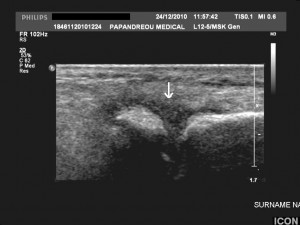

5. Ιερολαγονίτιδα: Η ιερολαγονίτιδα είναι συνήθως ετερόπλευρη και ασύμμετρη (εικ.3), ιδίως στα πρώιμα στάδια10. Μπορεί ωστόσο να εξελιχθεί και σε αμφοτερόπλευρη αγκύλωση. Ψωριασική οροαρνητική νόσος μπορεί να υφίσταται και χωρίς ιερολαγονίτιδα. Μέχρι και στο 50% των ΨΑ ασθενών μπορεί να εμφανισθεί διαχρονικά ιερολαγονίτιδα11.

Εικόνα 3: Ασύμμετρη ψωριασική ιερολαγονίτιδα με αρχόμενες, ήπιες διαβρώσεις των αρθρικών επιφανειών και εμφανή υπαρθρική οστεοπύκνωση.